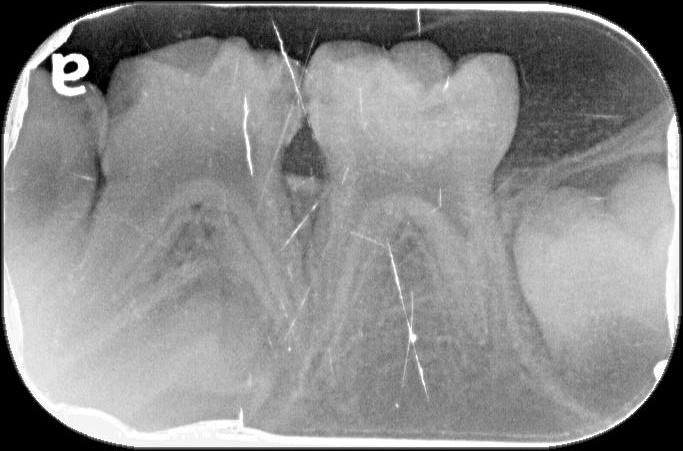

4살아이 눈으로도 시급한게 아래2개 위에 2개정도입니다.그런데 10개나 치료해야되고 8개를 크라운을 씌워야 된다고 하는데요 사진상에도 그런가요?

x-ray 사진상에서 치아와 치아 사이 충치가 있습니다. 어금니 치아와 치아 사이 충치는 눈에 잘 안보이지만 안으로 많이 진행된 경우가 많습니다.

2. 사진상에서 보이는 치아들은 충치가 있는게 다수이며 첫번째 사진의 오른쪽 치아, 세번째 사진의 왼쪽 치아는 충치가 심해보입니다.